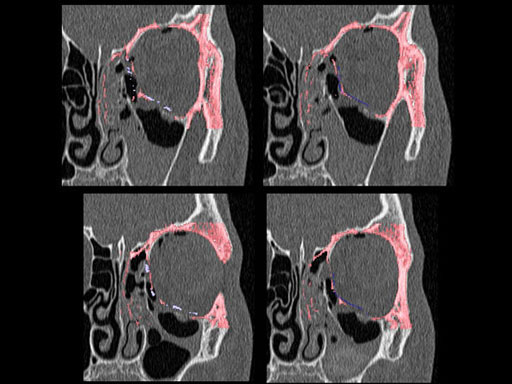

Furthermore, as orbital floor fractures are quite frequently associated with medial wall fractures; anatomic restoration especially in the transition zone between both wall is a demanding procedure. As described by B. Hammer, the orbital floor has an initial shallow convex section behind the rim, then inclines upward behind the globe, and inclines upward to meet the medial wall, creating a distinct bulge behind the globe. These convex curves of the medial wall and floor create a postbulbar constriction of the orbital cavity, which must be reconstructed when the orbit is rebuilt following fractures. Treatment is directed at precise anatomical reconstruction of orbital shape and volume in order to restore the correct position of the eye. To provide surgeons with an adequate implant that addresses the requirements of two wall acute orbital fractures or for secondary reconstruction of enophthalmos and dystopia, a new series of preformed orbital plates was developed for the new orbital matrix system.

These pre-formed orbital plates were developed based on the evaluation of more than 3000 CT scans of patient data and then reduced to 279 in order to find anatomical averages. In the end it was possible to reduce the number of plates down to two per side and still match the vast majority of all patients including males and females.

Unlike the existing two-dimensional mesh implants, the geometry of the new preformed plates will be adequate to match the individual anatomic situation of the patient in almost any case. However, the mesh parts can be individually adjusted if necessary. In these cases the solid part in the central posterior area needs to remain untouched. Areas of the orbit that do not require a bridging can be spared out by trimming the implant along the designated cutting lines in the height of the medial wall and/or length of the orbital floor area. The lateral anterior part of the plate is intentionally pre-bent higher than the orbital rim anatomy to allow free plate movement during plate positioning.

Implant placement according to the orbital landmarks

1 Orbital rim, 2 Inferior orbital fissure, 3 Posterior orbital ledge, 4 Transition between the medial wall and orbital floor, 5 Optic canal, 6 Lacrimal fossa